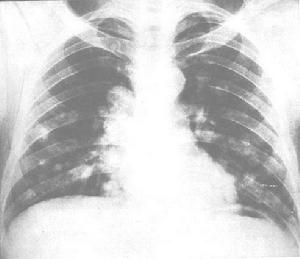

2.CT 檢查 對氣管腫瘤的診斷有很大幫助。CT 可顯示氣管腔內的密度增高的軟組織影,多為偏心性,氣管壁增厚,氣管呈不規則狹窄,大約10%的氣管腫瘤沿氣管周圍生長,30%~40%的氣管腫瘤直接累及縱隔。支氣管腫瘤在CT 上可表現為向腔內生長或向腔外浸潤,引起支氣管不全或完全梗阻,出現阻塞性肺炎或肺不張,根據支氣管腫瘤的浸潤程度,Naidich 等將其分為6 種表現:①支氣管壁顯示正常;②支氣管壁均勻狹窄;③支氣管不規則狹窄;④支氣管腔完全阻塞;⑤支氣管腔內腫塊;⑥支氣管受壓移位。

氣管腫瘤早期出現喘憋極易誤診為支氣管哮喘,因為肺和胸部的X 線檢查難以觀察到氣管腔內的病變,直至病人出現喘鳴、呼吸困難、發紺等症狀才明確診斷。可行CT 或MRI 和氣管鏡檢查。治療方案